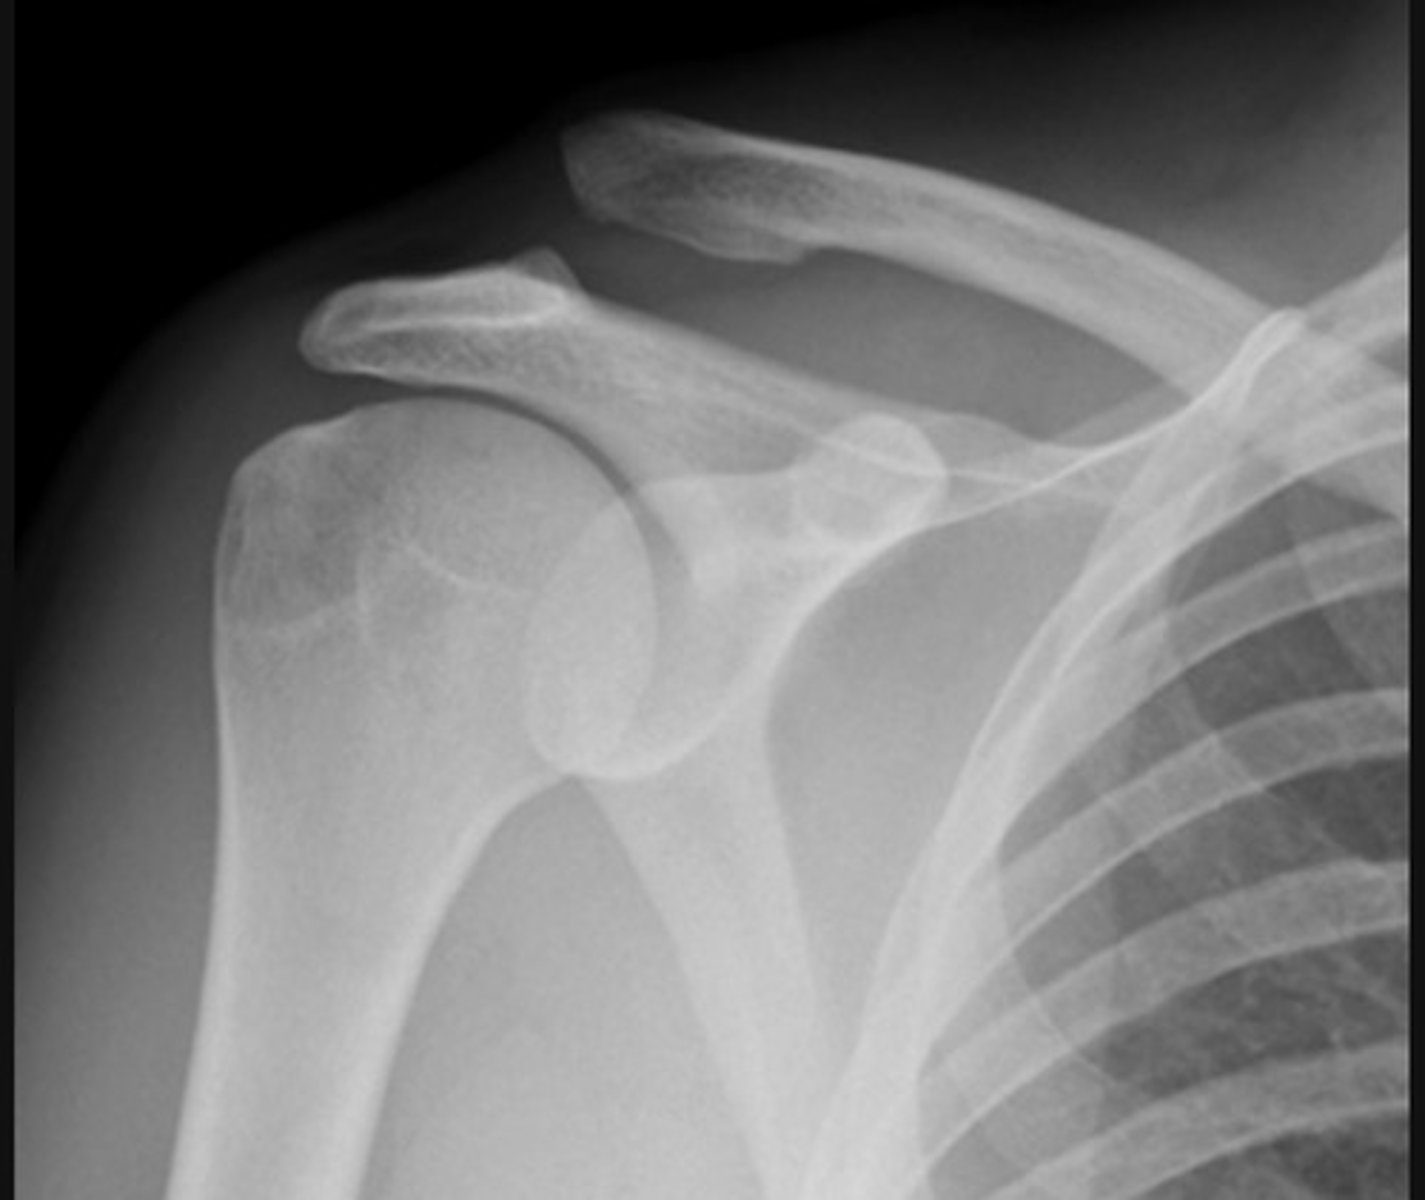

Anterior dislocation and Hill-Sachs lesion

Anterior dislocation and glenoid fracture (bankhart lesion)